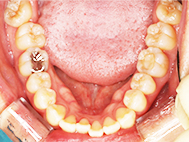

Before

| 症状 | 上下前歯叢生 |

| 治療内容 | 上顎部分裏側矯正 下顎は目立ちにくい透明な装置 |

| 治療期間 | 11ヶ月 |

左上の前歯内側に入っている下の前歯ガチャ歯

左上前歯が下の歯の内側に入っているのが気になるとの事で来院されました。目立たない矯正治療を希望しているとのこでした。 上顎の装置は、歯の裏側(リンガル装置)で下顎は表側で矯正治療を行いました。口を閉じた時、上の前歯が内側に入っている為に下の歯を前に押し出している状態でした。その為、上の歯を前に出すだけではその歯が下とのかみ合わせの関係で、前に飛び出すような治療となってしまいます。 今回の症例ではシュミレーションを見て頂き、下の歯も治療し、内側へ下げることによって上の歯も飛びだすことなく、キレイにおさまることを説明し、上下一緒に矯正することをお勧めさせて頂きました。